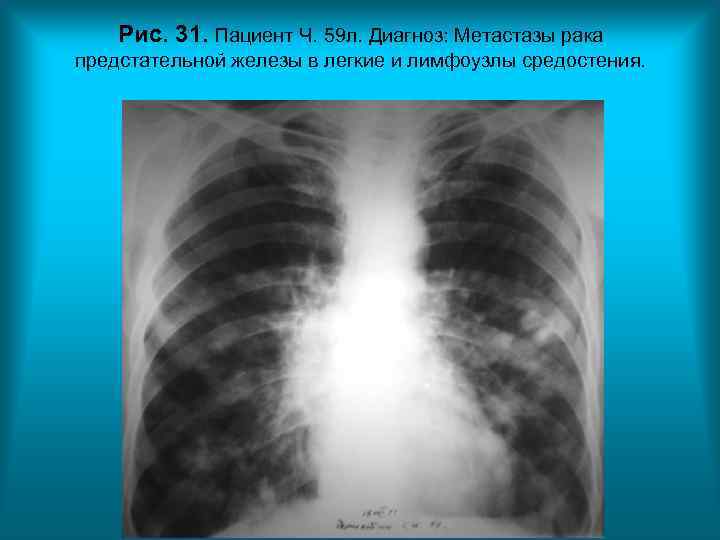

Рис. 31. Пациент Ч. 59 л. Диагноз: Метастазы рака предстательной железы в легкие и лимфоузлы средостения. Н. С. Воротынцева. С. С. Гольев Рентгенопульмонология